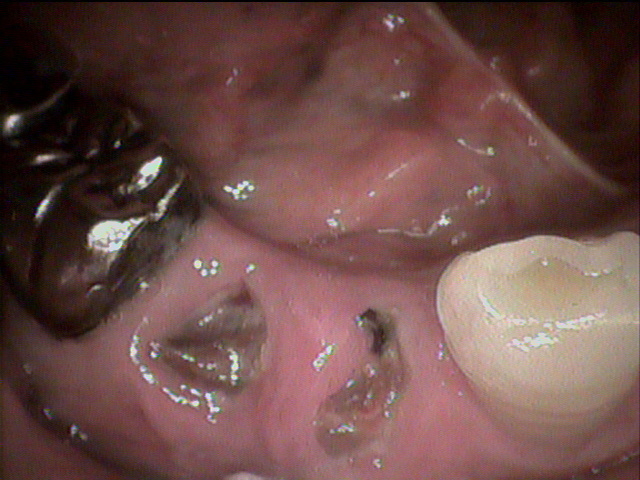

上の入れ歯がこわれてしまって、来院されました。のこっている上の前歯の6本分がつながったブリッジは歯ぐきが根元ではれていてぐらぐら状態。全く噛む場所がありません。

診断すると、残っている前歯4本は歯の中がほとんどくさってしまっていました。

残念ながら前歯はすべて抜かなくてはならず、上の歯は総入れ歯としてまず治療用入れ歯を事前に準備することから開始しました。同時に歯ぐきの腫れの消炎処置をしました。

前歯のつながった歯を切り離し、同時に歯を抜き、その日にすぐに仮の入れ歯を装着することとしました。

顎の粘膜の調整をしながら経過し、上の入れ歯との噛み合わせを調整していきます。

顎の状態が良好になってきました

約2ヶ月後最終入れ歯を入れた状態です。

初診から最終調整まで、前歯がなくなってしまう見栄えが悪い事は一日もなく治療を進行することができました。

現在 右も左もしっかりと噛む事が出来ます。